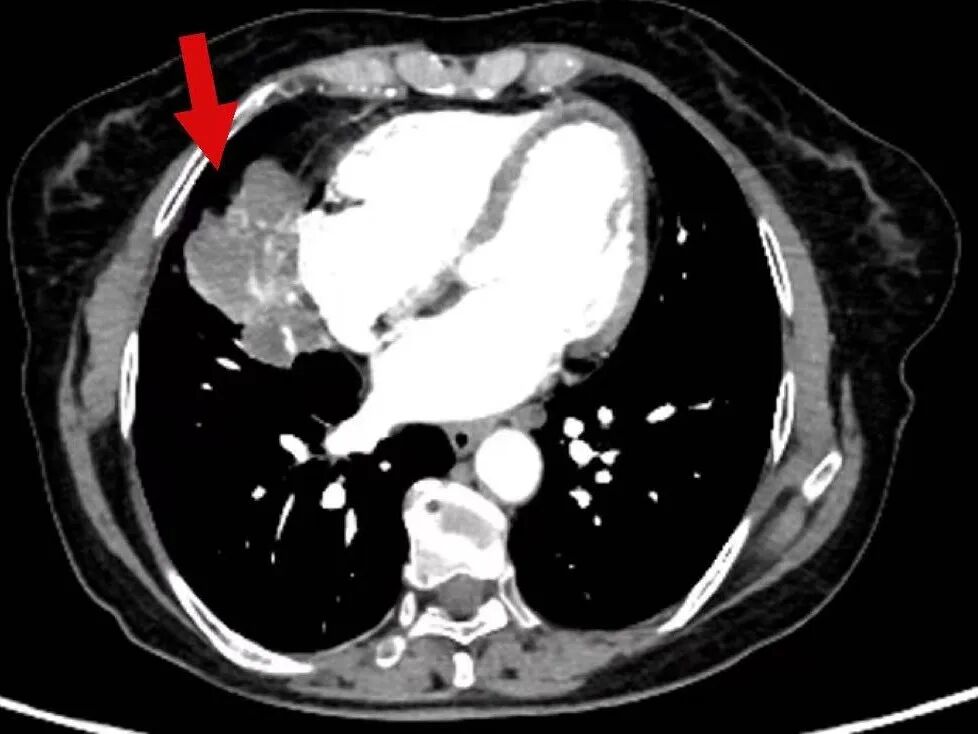

2025年3月17日,肿瘤诊疗中心团队首次为毕女士成功实施BACE治疗。术后患者病情暂时稳定,但5月10日复查显示肺部原发病灶稳定,肝脏转移病灶再次增大。

令人鼓舞的是,治疗一个月后复查显示,毕女士肺部和肝脏的肿瘤明显缩小,病情得到有效控制,生活质量显著改善。出院时,毕女士激动地说:“本来以为病情已经没希望了,是中山医院的专家们没放弃我,一次次调整方案,现在我不仅不怎么难受了,还能正常生活,真的太感谢他们了!

在玉溪市中山医院肿瘤诊疗中心治疗后,肿瘤在明显缩小